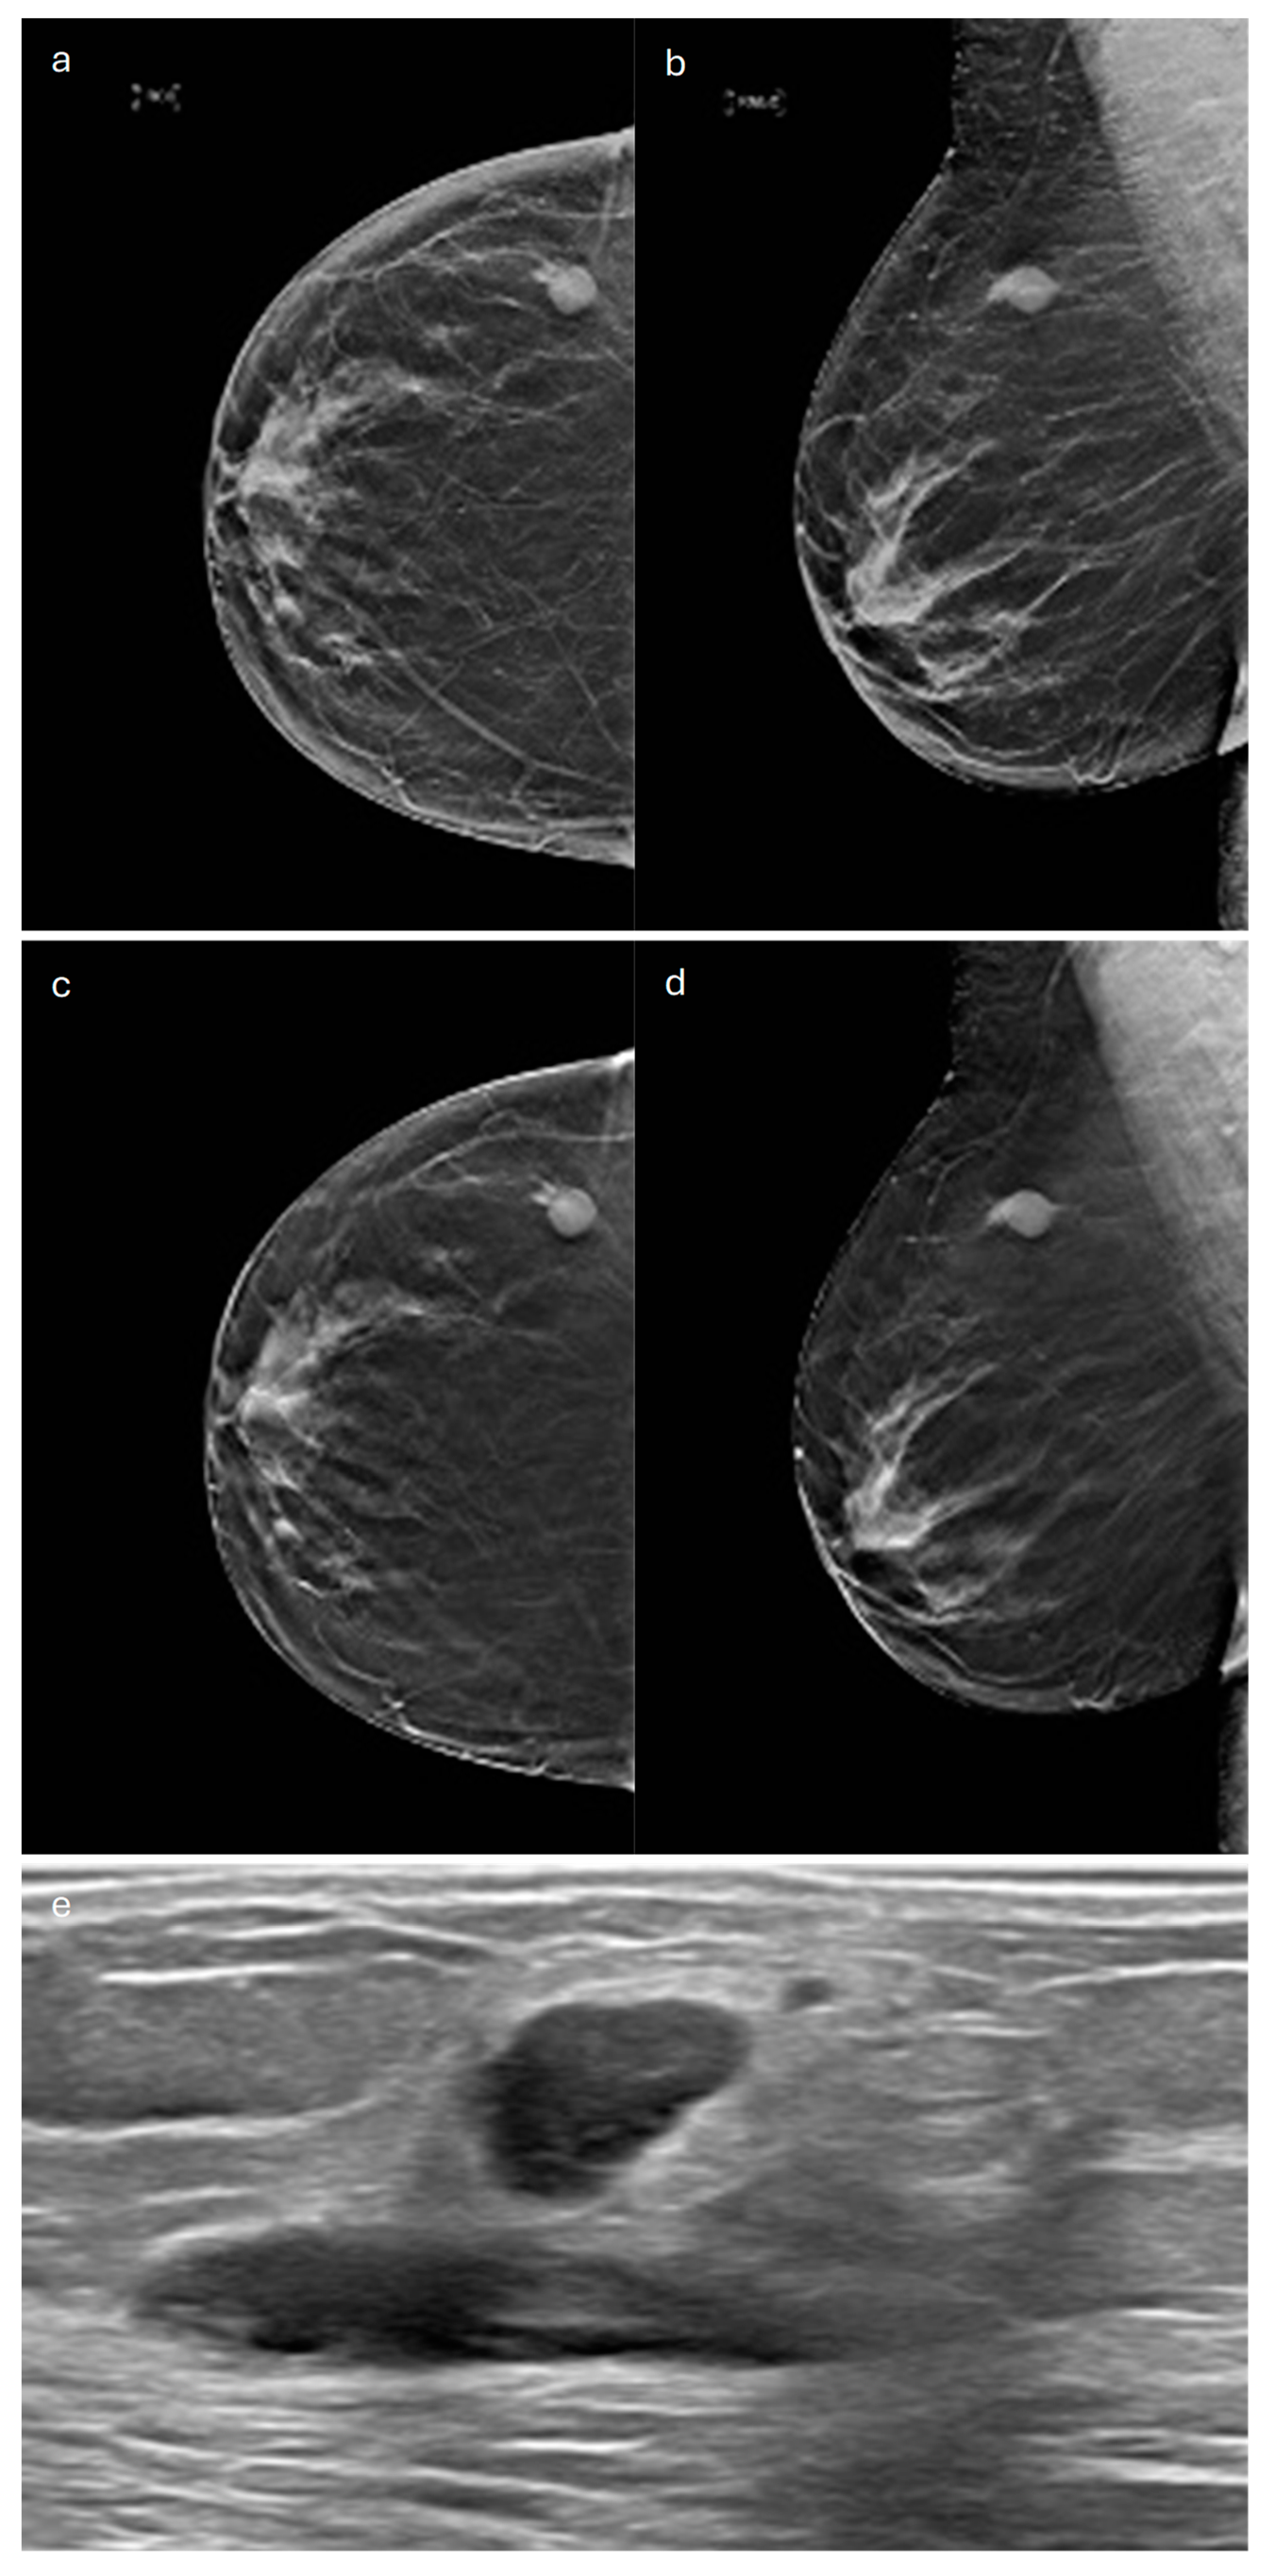

4. Mucinous